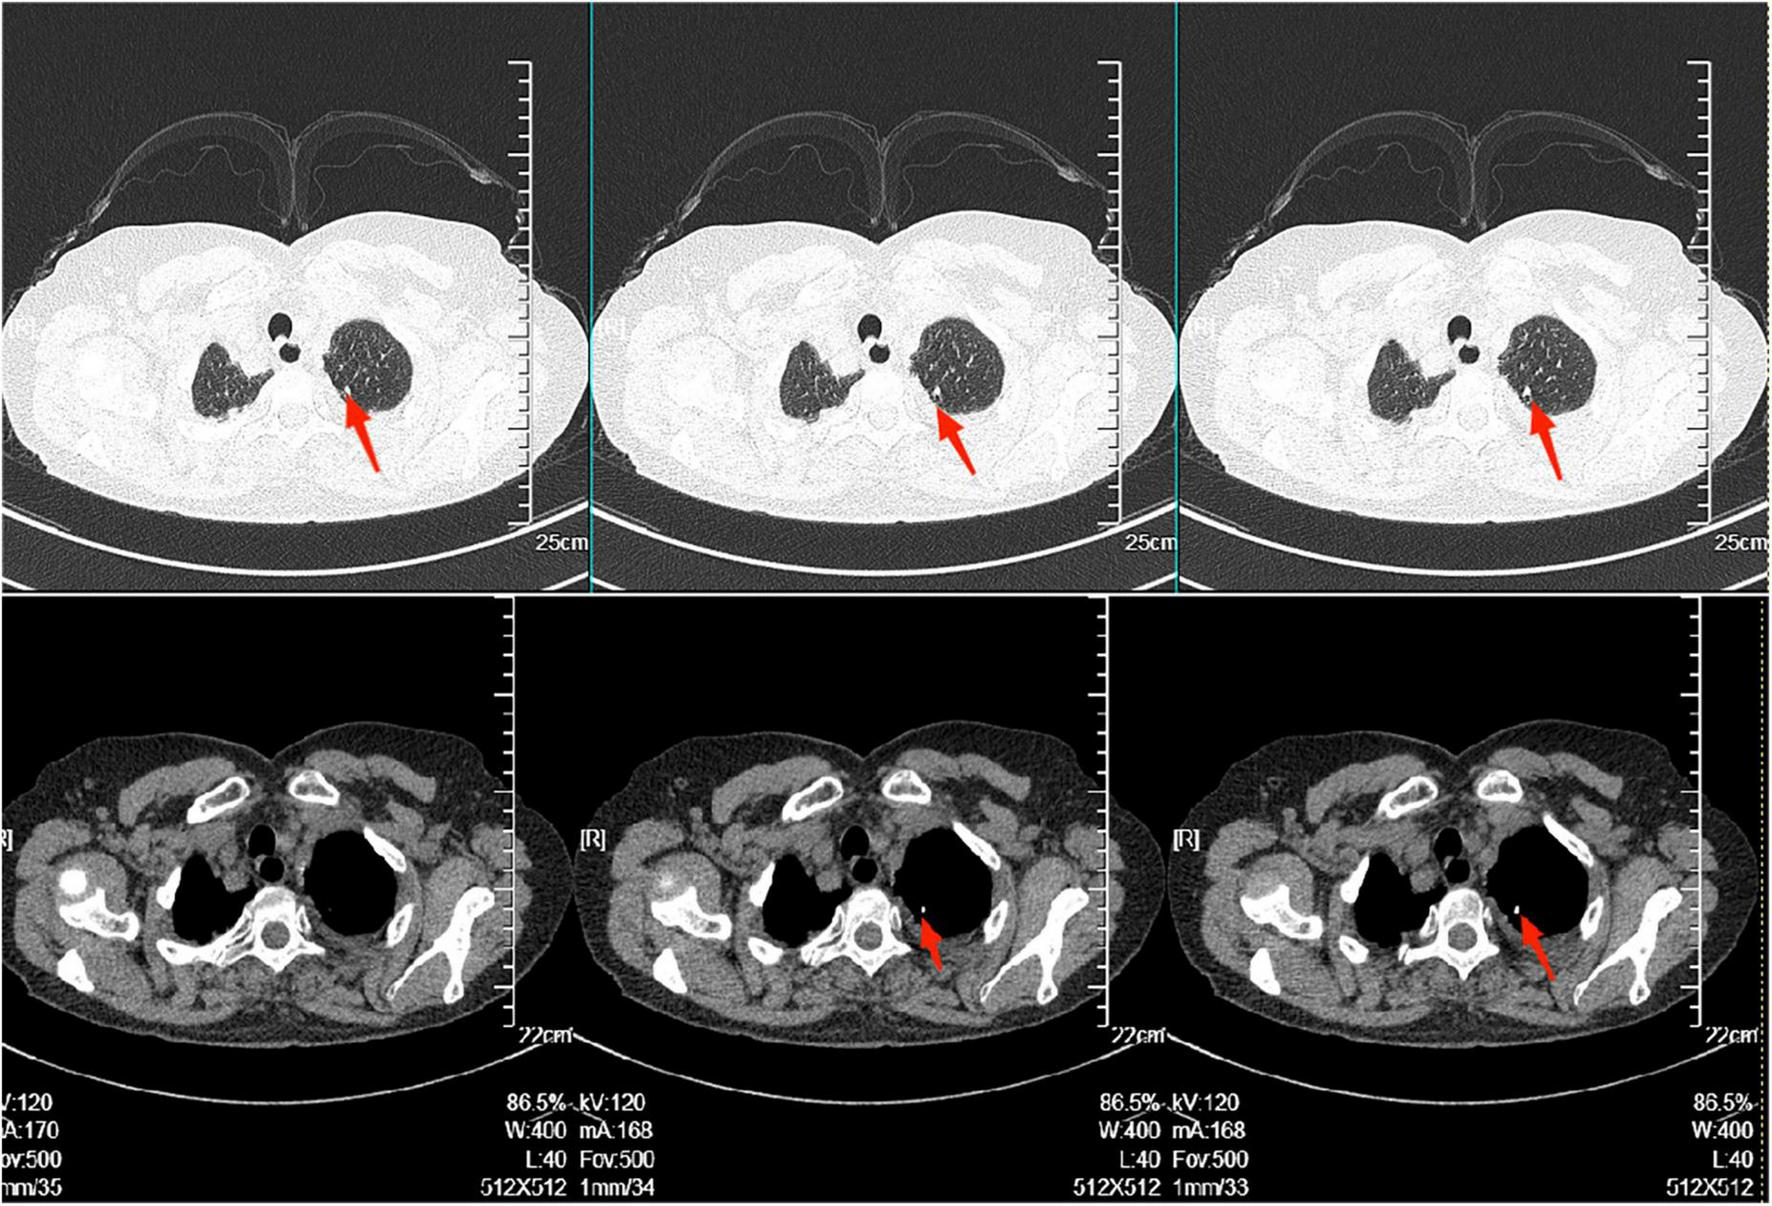

The electrocardiogram (Figure 1) suggested a sinus heart rate with low voltage in the limb leads. The patient’s laboratory data at admission are shown in Table 1. Echocardiography indicated moderate to severe pericardial effusion (Figure 2), and echo-free areas were seen in the pericardial cavity. The diastolic fluid width was measured as 14 mm in the anterior wall of the right ventricle, 16 mm in the posterior wall of the left ventricle, 19 mm in the lateral wall of the left ventricle, and 20 mm in the apical part of the left ventricle. A bedside color doppler ultrasound showed bilateral pleural effusions. After admission, the patient had a fever intermittently, with a temperature of up to 38.3°C without chills and shivering. The patient’s temperature was elevated within 24 h of admission, meaning that the possibility of community-acquired pneumonia could not be excluded. After blood cultures were retained, the patient was also given empirical anti-infective treatment with moxifloxacin. However, as the patient’s improvement in relevant tests was considered not to exclude tuberculosis, the use of fluoroquinolones alone should be avoided, and the patient’s moxifloxacin was discontinued and changed to ampicillin. The patient’s blood culture later indicated no bacterial growth. A computed tomography (CT) scan of the lungs revealed sporadic inflammation in both lungs, inflammatory nodules in the upper left and lower right lung lobes, calcification in the upper left lobe (Figure 3), and bilateral pleural effusions. Furthermore, the mediastinal lymph nodes were enlarged and partially calcified. Pericardiocentesis and drainage were used to relieve the patient’s symptoms, such as chest tightness and shortness of breath. The patient’s pericardial effusion was hematogenous, with routine results as follows: protein 53.96 g/L; Reye’s test positive; total erythrocyte count 214300.00 × 106/L; total leukocyte count 3762.00 × 106/L; percentage of single nucleated cells 84%; adenosine deaminase (ADA) 32.0 U/L; lactate dehydrogenase (LDH) 326 U/L; and carcinoembryonic antigen (CEA) 0.47 ng/ml.

FIGURE 3

There was scattered inflammation in both lungs, inflammatory nodules in the upper left and lower right lobes. Calcification in the left upper lobe, as shown in the red arrow in the figure. The radiologist considered it to be stable tuberculosis.